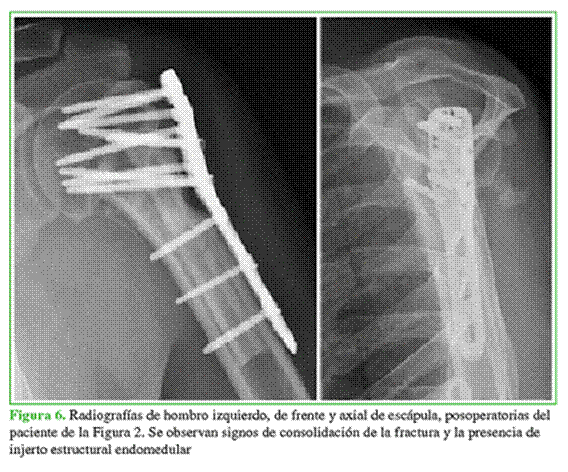

Se utilizó aloinjerto estructural de radio en 10 casos y de cúbito en dos casos, provenientes del banco de huesos de nuestro Centro. Luego de visualizar una reducción correcta y estable en el intensificador de imágenes, se aplicó una placa bloqueada anatómica para húmero proximal AZ (South America Implants, Buenos Aires, Argentina). Se fijó la placa con tornillos corticales bloqueados que atravesaban el AOEE y, siempre que fue posible, al menos, un tornillo con dirección al calcar (Figuras 5 y 6).

Al terminar la cirugía se colocó el miembro afectado en un cabestrillo por cuatro semanas y se administró un antibiótico profiláctico en las primeras 24 h posteriores a la cirugía. En el primer día posoperatorio, se iniciaron los movimientos pendulares y de flexo-extensión del codo. Luego, se indicaron ejercicios de movilidad pasiva y activa asistida a las tres semanas, y ejercicios de movilidad activa a las seis semanas. Los controles clínicos y radiográficos se realizaron a las 2 y 4 semanas, a los 2, 3, 6 y 12 meses, y luego anuales.